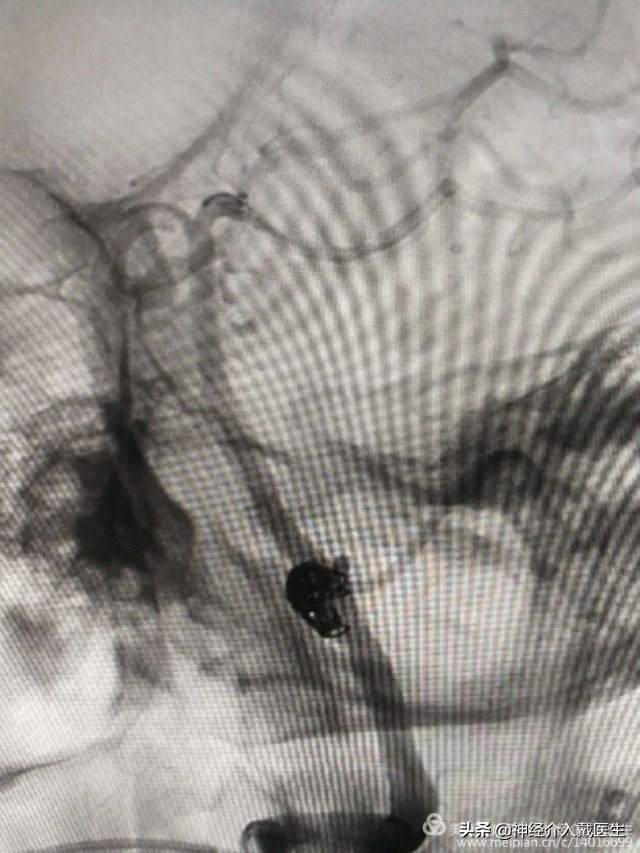

脑血管造影显示右侧椎动脉V4段动脉瘤,并且是比较少见的夹层动脉瘤。长度大约9mm,动脉瘤破口与右侧椎动脉重要分支右侧小脑后下动脉很近。

动脉瘤手术经典治疗方式有开颅夹闭术和介入栓塞术,该动脉瘤位于后循环,后颅窝,脑干附近,显露困难,并且是夹层动脉瘤,开颅夹闭术不合适,介入栓塞术是最好的选择,该动脉瘤位于椎动脉重要分支右侧小脑后下动脉开口处,所以保护右侧小脑后下动脉是手术的重中之重。仔细观看3D,动脉瘤破口与右侧小脑后下动脉开口还是有一定的距离,又是破裂动脉瘤,支架加弹簧圈栓塞是最好的选择,必要时可以用微导管或者支架保护右侧小脑后下动脉。

通过真腔放置支架导管,放置弹簧圈导管,释放一个5mm*12cm弹簧圈后,考虑需要保护小脑后下动脉,支架网孔大小很重要,我们选择Enterprise2支架,4mm*23mm一枚,

依次释放6mm*9cm,4mm*8cm,2mm*2cm,2mm*2cm弹簧圈各一枚,造影显示动脉瘤腔致密栓塞。